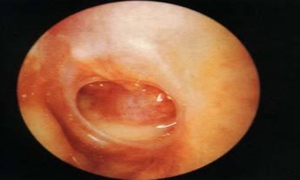

本病在鼓膜穿孔前后的表现有所不同:早期的主要症状为耳痛,可伴有发热、听力下降,此时鼓膜红赤、完整;随后鼓膜紧张部穿孔,有脓液自穿孔处流出,耳痛逐渐缓解,而听力下降加重。久病者,主要症状为耳内反复流脓或持续流脓,听力下降,鼓膜紧张部或松弛部可见大小不等的穿孔,通过穿孔有时可见到鼓室的肉芽或灰白色胆脂瘤。